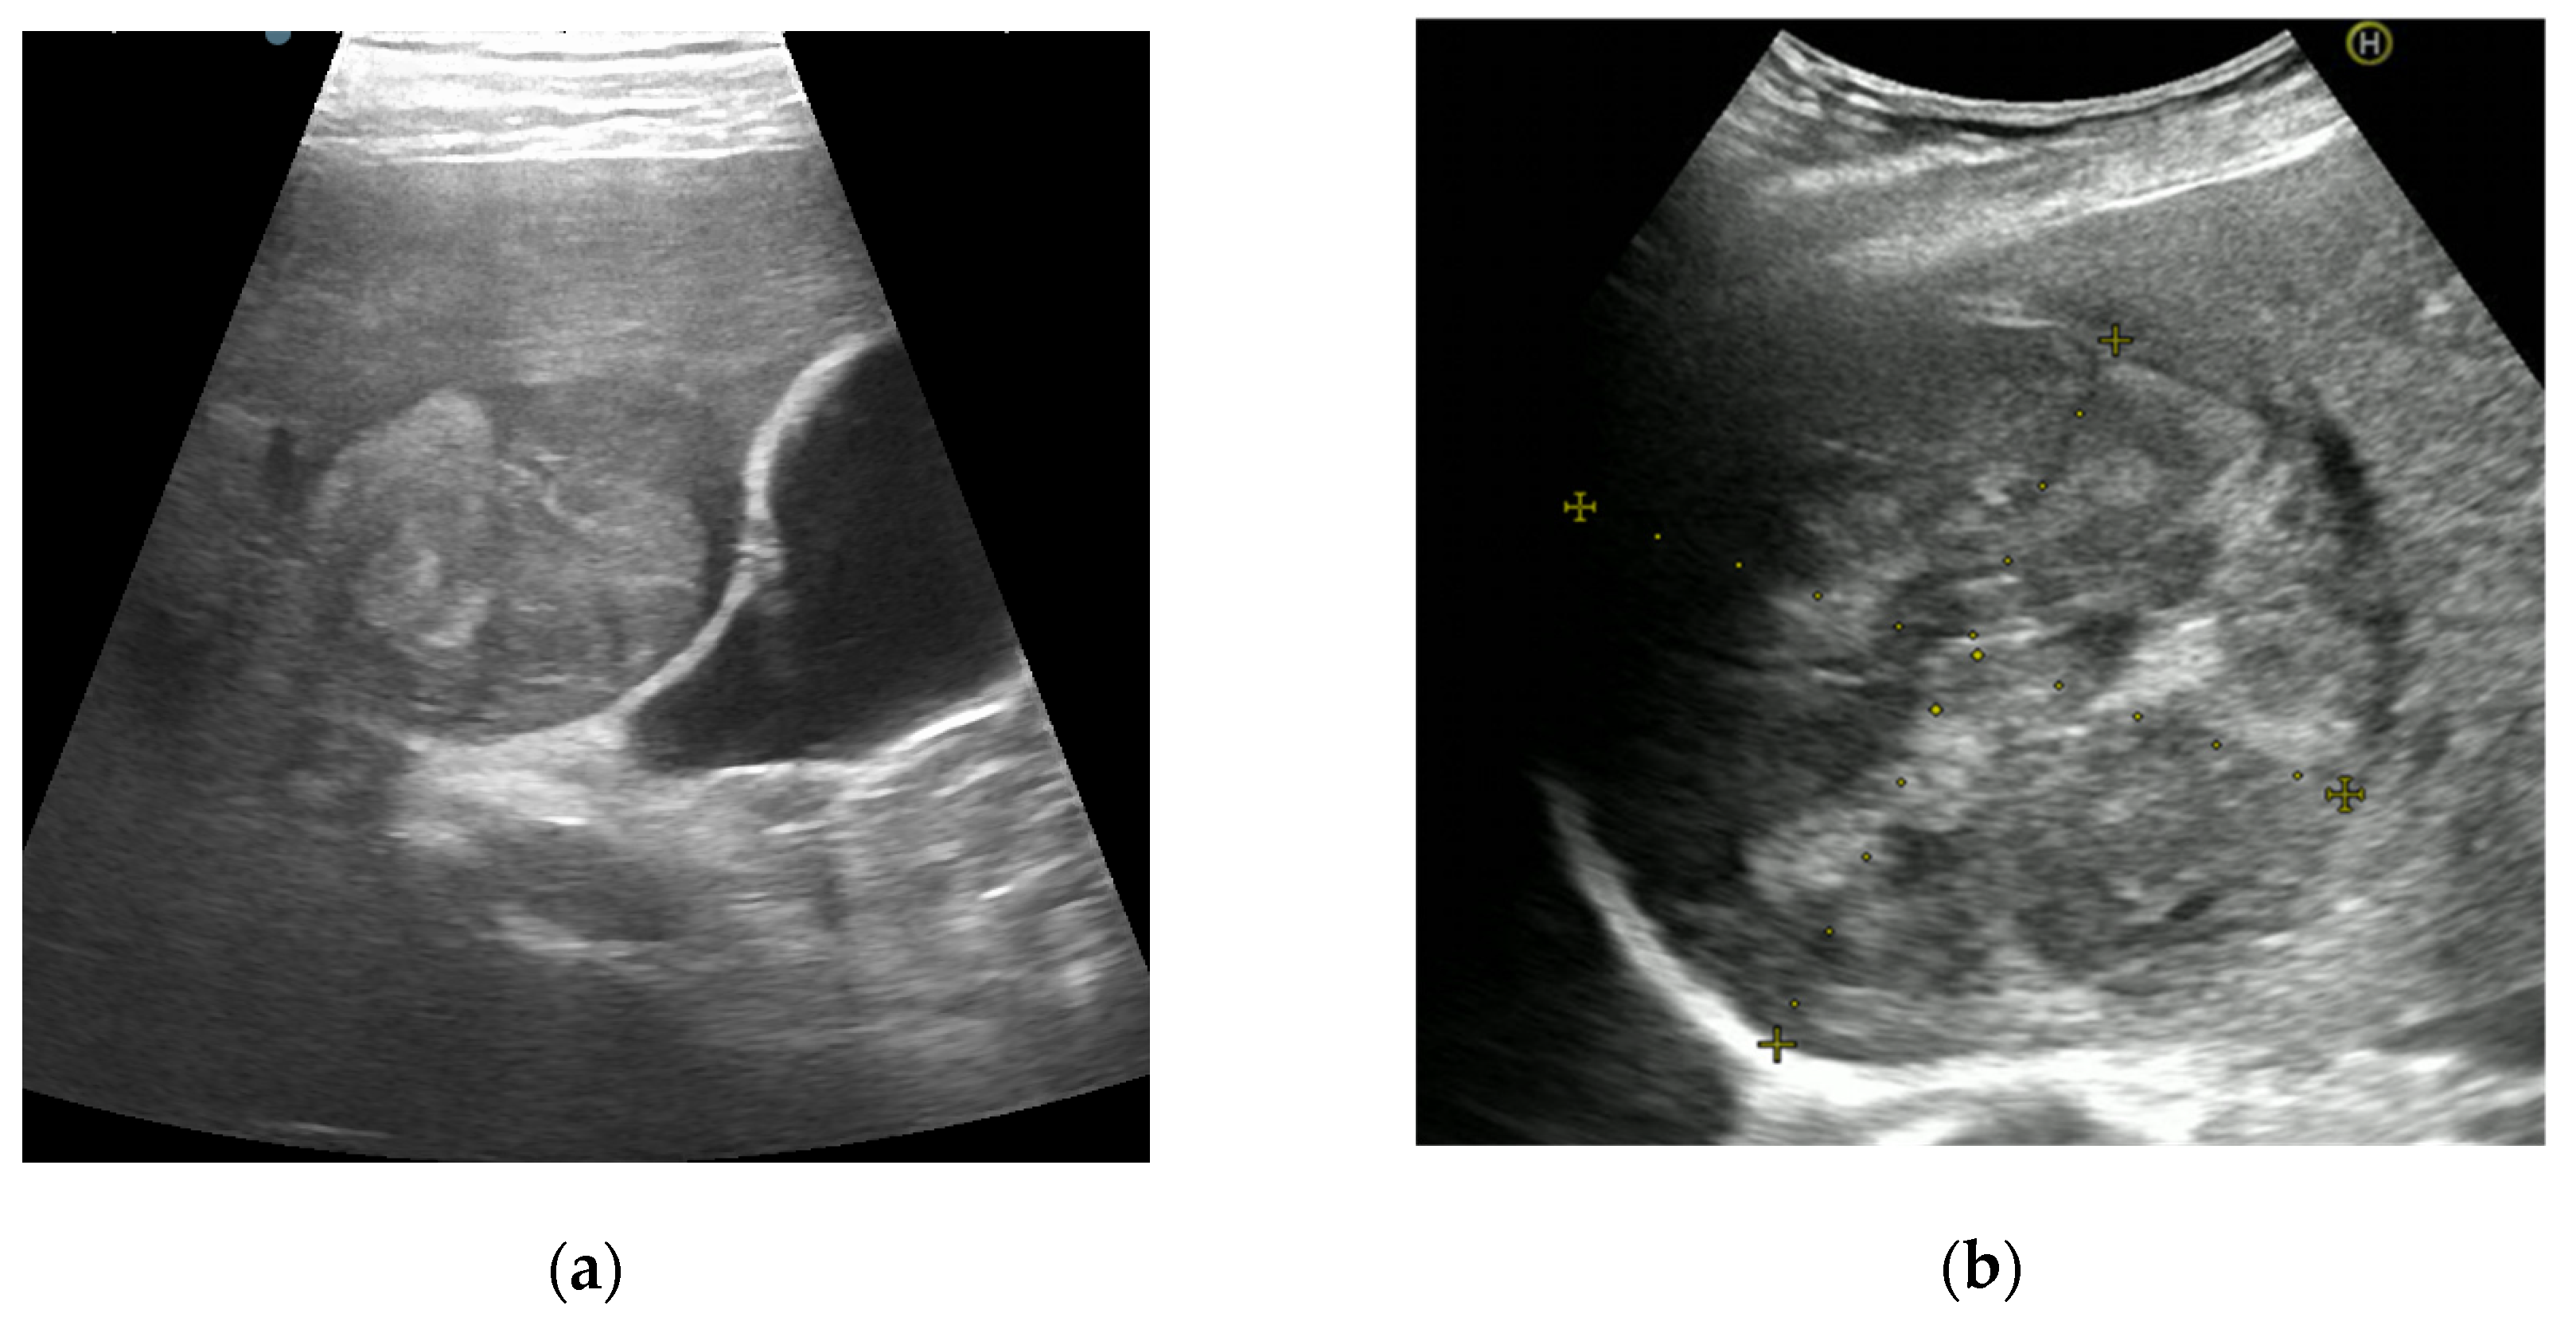

3.1. CEUS

3.1.1. CEUS Patterns According to LI-RADS Recommendations